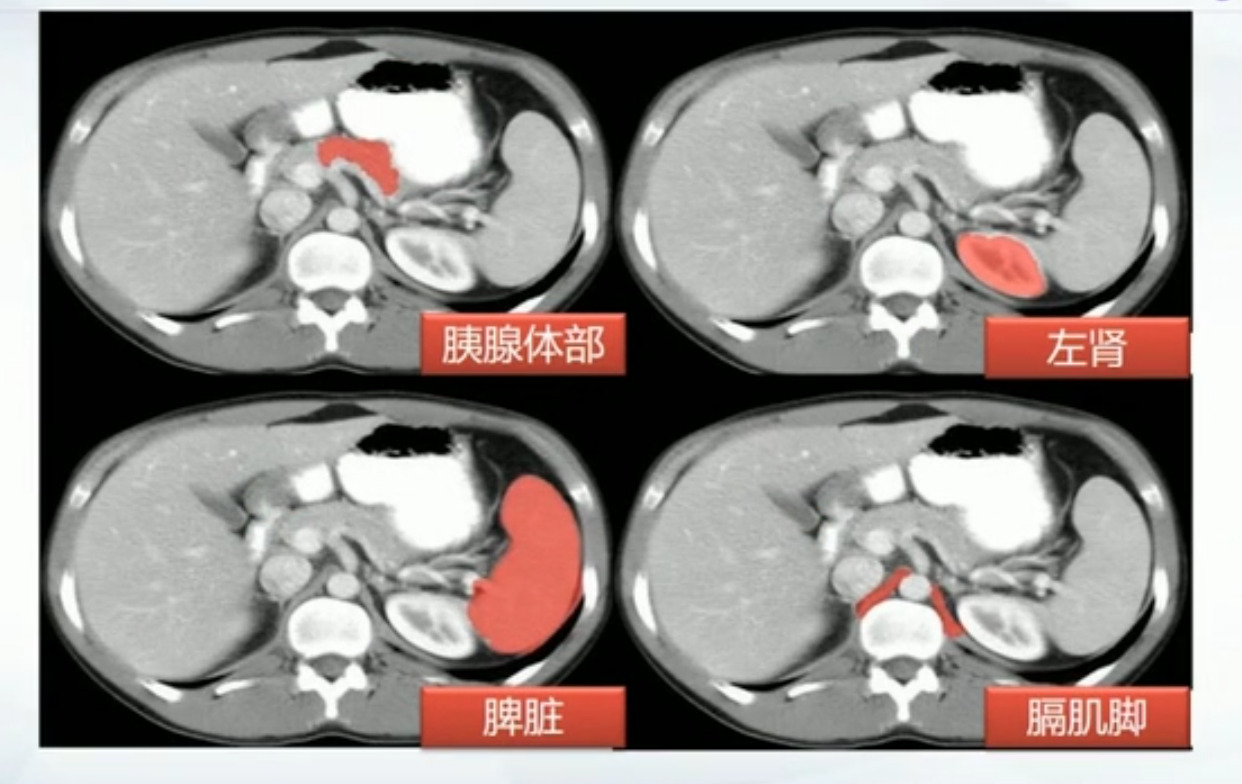

肝CT

- 40~60HU,高于胰,脾

- 肝内管道系统(胆管,肝动脉静脉和门静脉)低于实质,周围小分支多不显示。大血管呈低密度树状影

正常肝重要结构